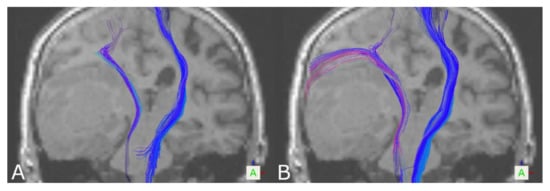

3.1. The Corticospinal Tract